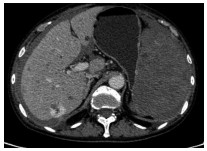

A case of primary splenic angiosarcoma

CHEN M, ZHA YF, WANG YY, et al. CT findings of primary splenic angiosarcoma and literature review[J]. J Pract Radiol, 2019, 35(1): 159-161. DOI: 10.3969/j.issn.1002-1671.2019.01.041.

陈明, 查云飞, 王艳艳, 等. 原发性脾血管肉瘤CT表现并文献复习[J]. 实用放射学杂志, 2019, 35(1): 159-161. DOI: 10.3969/j.issn.1002-1671.2019.01.041.